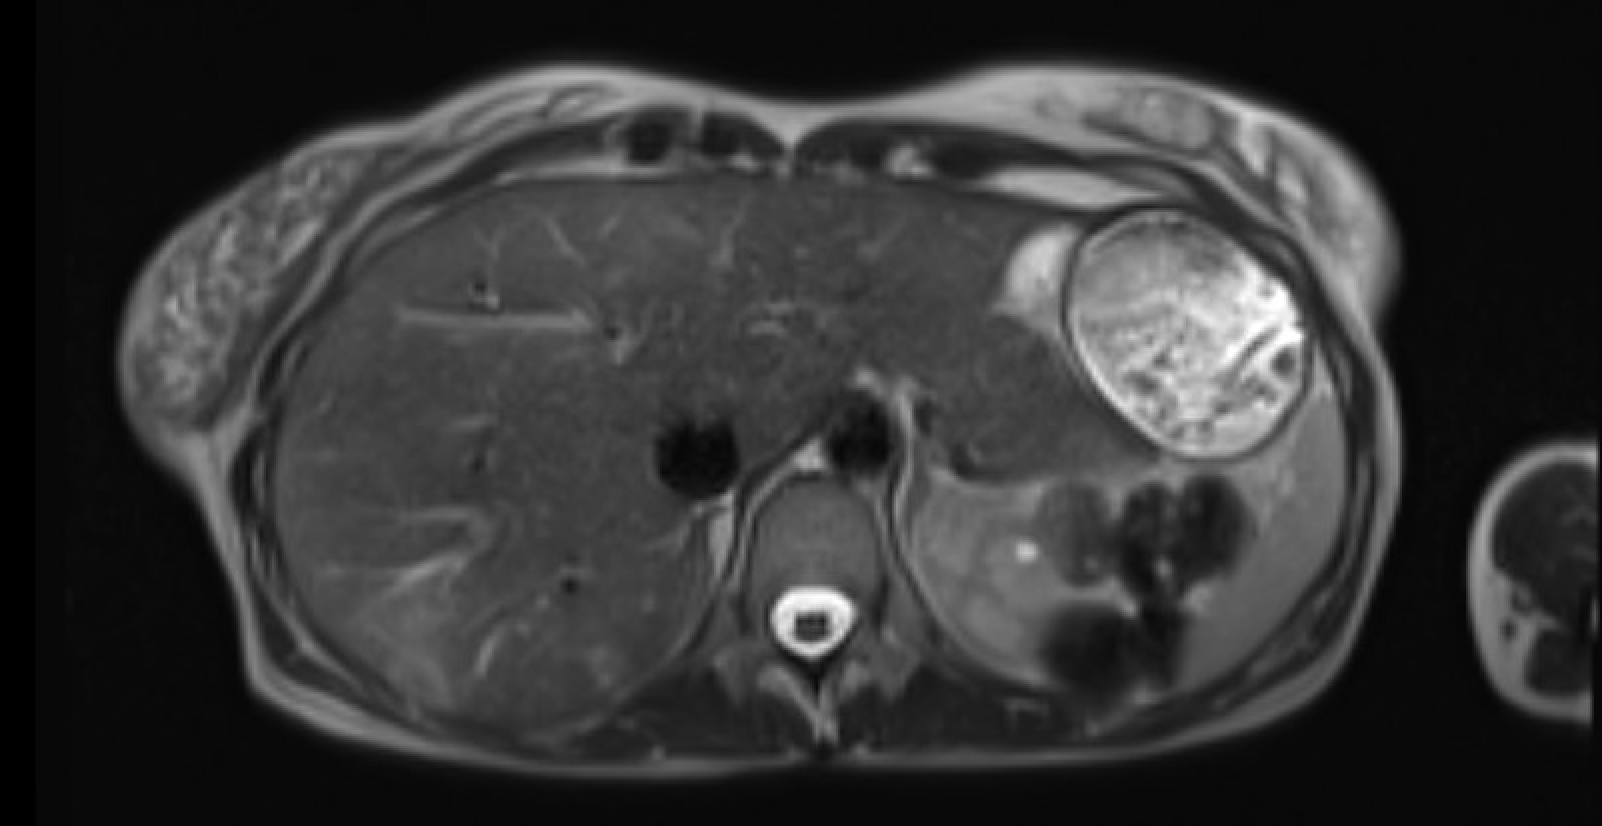

Spontaneous renal hemorrhage

(Wünderlich syndrome)

Subcapsular/perirenal T1-hyperintense collection with T2 signal heterogeneity. Subtraction images mandatory to exclude underlying enhancing neoplasm (AML, RCC most common causes)